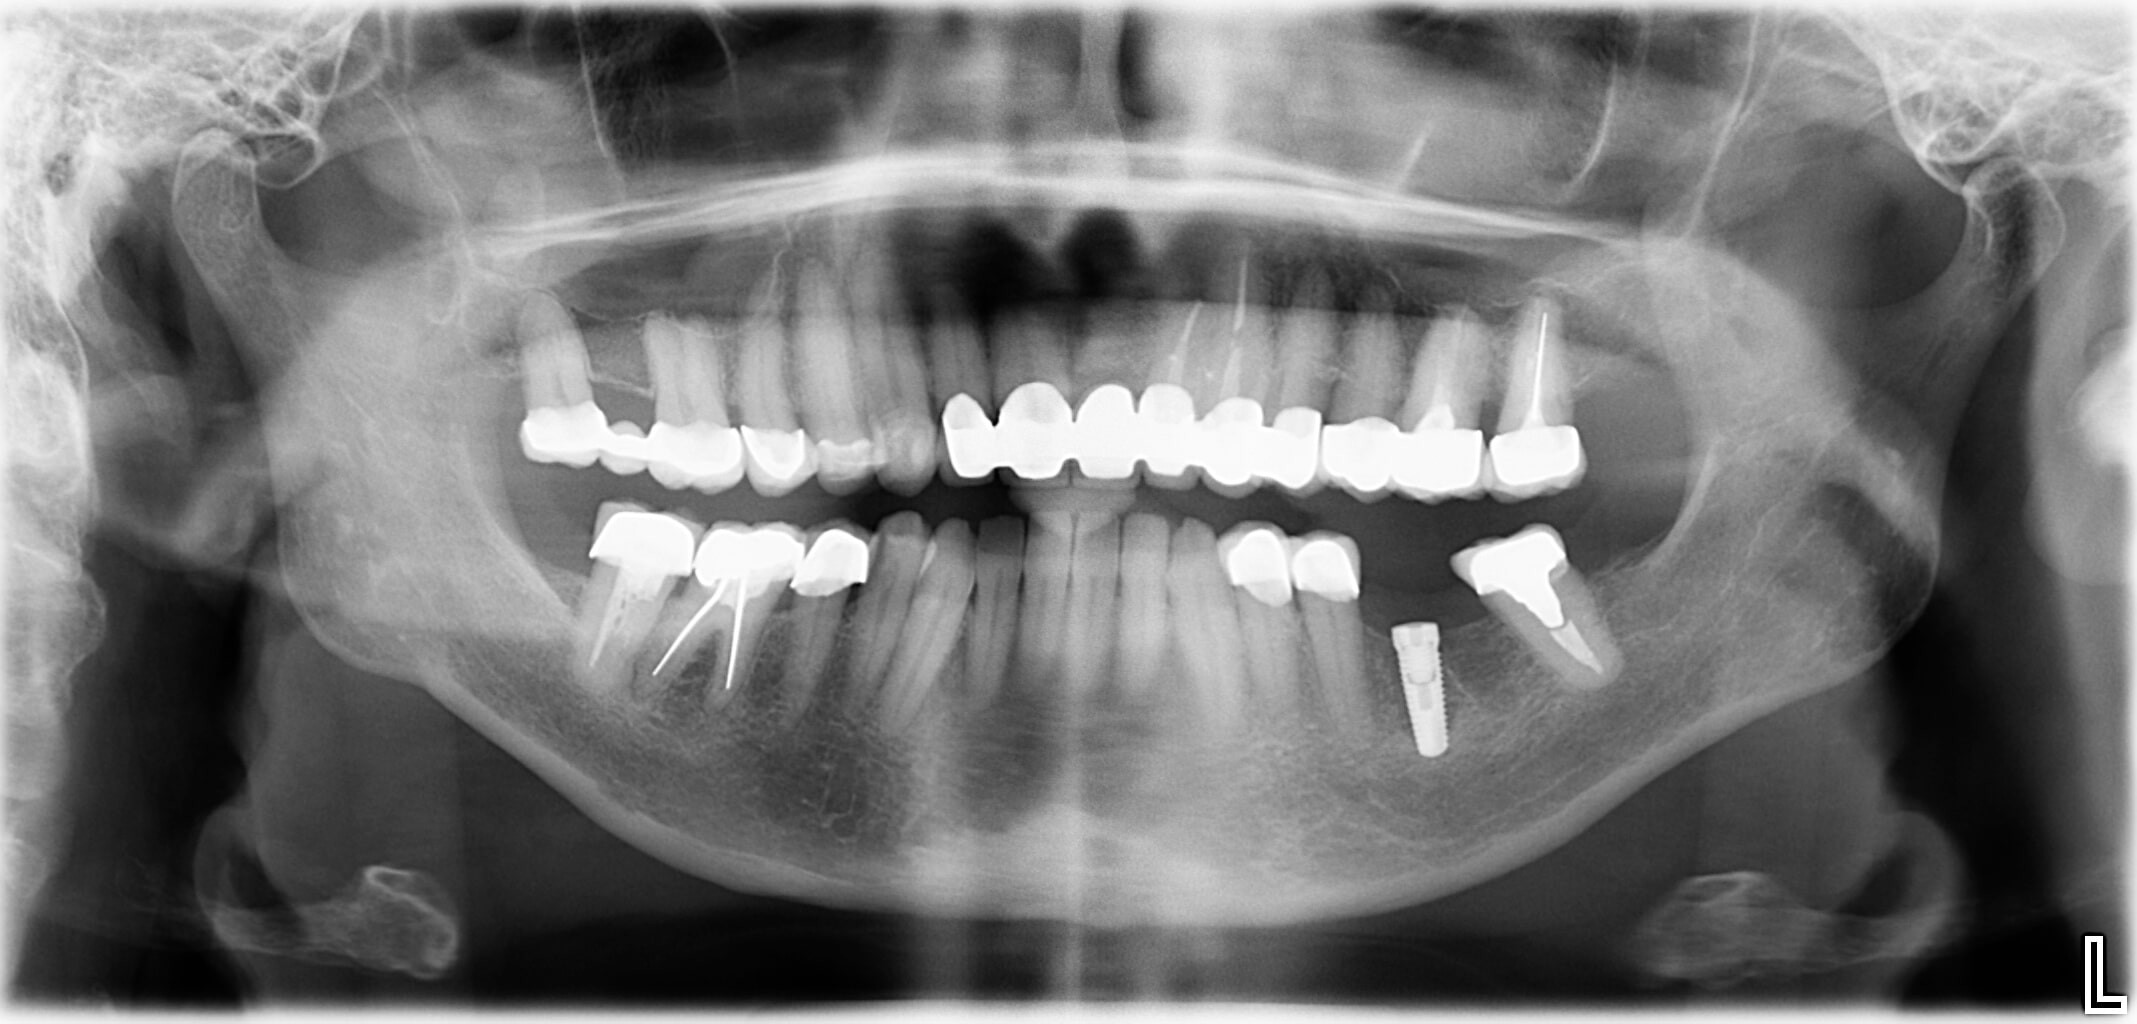

- Implantatgetragener Zahnersatz anstelle einer Brücke oder herausnehmbarer Teilprothese

- Fehlende Zähne werden Zahn-für-Zahn mit Implantaten ersetzt

Das Resultat überzeugt

- Beschleifen gesunder Nachbarzähne entfällt

- Kein Kieferknochenabbau

3D-Ausblick

Mit unserer 3D-Röntgen-Technik sehen Sie Ihr Ergebnis schon vorab! So wissen Sie immer, worauf Sie hinarbeiten.